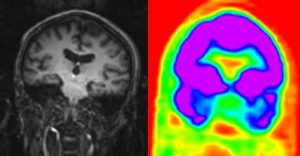

Before registration

AfterRegistration